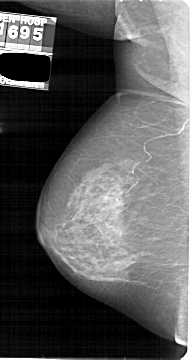

A_1889_1.RIGHT_MLO

RIGHT_MLO LINES 5266 PIXELS_PER_LINE 2836 BITS_PER_PIXEL 12 RESOLUTION 43.5 OVERLAY